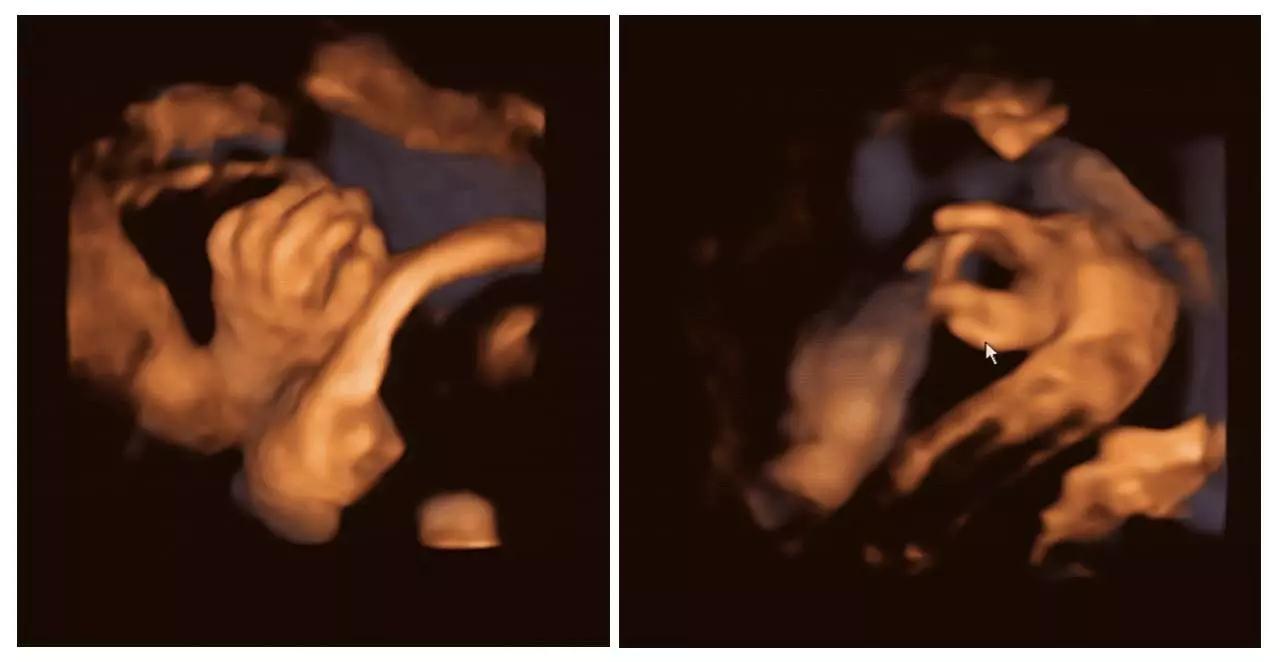

(图片来源于艾玛妇产)